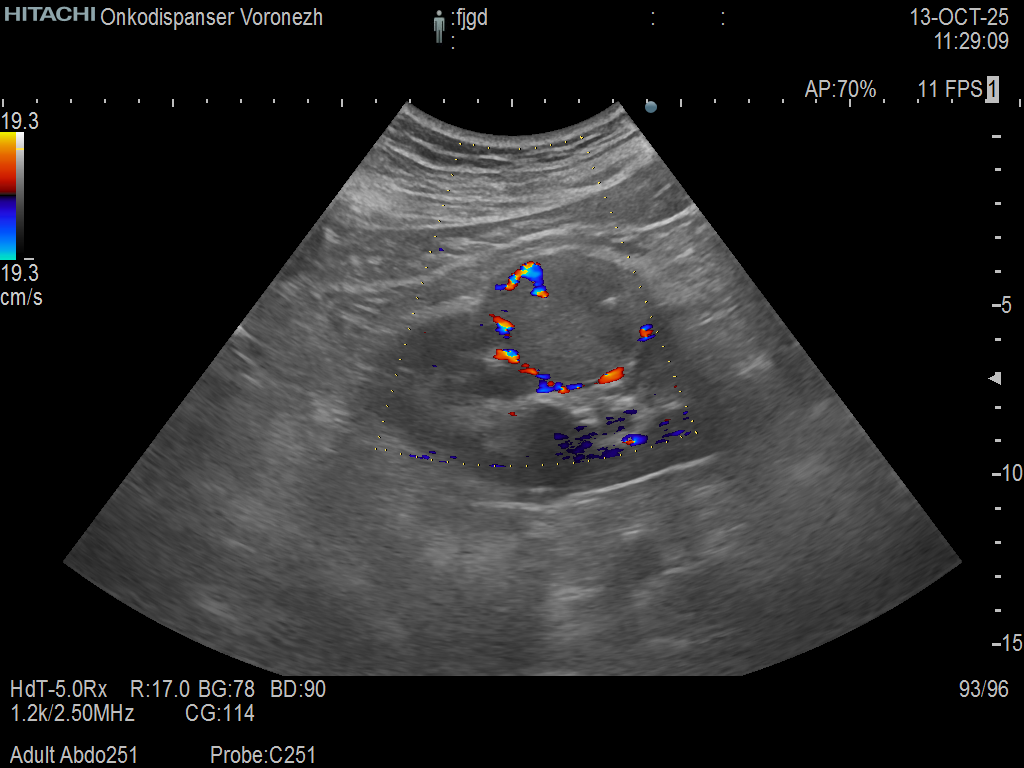

- Ультразвуковое исследование